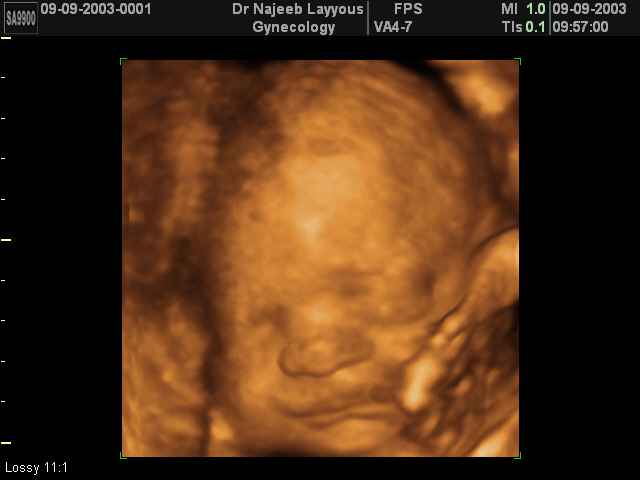

صور لوجه الجنين بجهاز الالتراساوند ثلاثي الأبعاد | الدكتور نجيب ليوس

صور لوجه الجنين بجهاز الموجات فوق صوتية ثلاثي الأبعاد